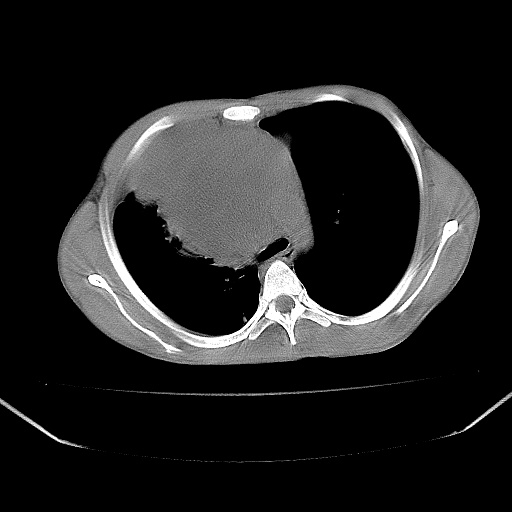

以下是引用zjzjr在2008-7-20 12:57:00的发言:[br]考虑为生殖源性肿瘤(内胚窦瘤),侵袭性胸腺瘤可能性大;右侧少量胸腔积液。

以下是引用xinliheng001在2008-7-20 21:17:00的发言:[br]右纵隔巨大分叶状软组织均质密度肿块,右上肺叶受压明显,纵隔右移、胸膜受累有少量积液和结节样增厚。应增强扫描一定会有更具诊断价值的信息。

以下是引用xinliheng001在2008-7-20 21:17:00的发言:[br]右纵隔巨大分叶状软组织均质密度肿块,右上肺叶受压明显,纵隔右移、胸膜受累有少量积液和结节样增厚。应增强扫描一定会有更具诊断价值的信息。